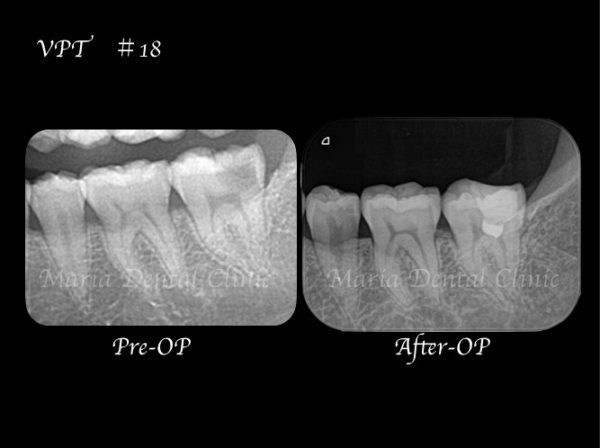

診査の結果、虫歯の進行はレントゲン上歯髄まで達していると思われましたが、厳密な歯髄診査の結果、診断は可逆性歯髄炎であり、生活歯髄保存療法が適応になると判断いたしました。

軟化象牙質(虫歯)を完全に除去した後に、歯髄を2mm程切断し、MTA(歯科用コンクリート)を充填しました。

2週間後の2回目来院時に生活歯髄反応が正常であることを確認し最終補綴に移行しました。